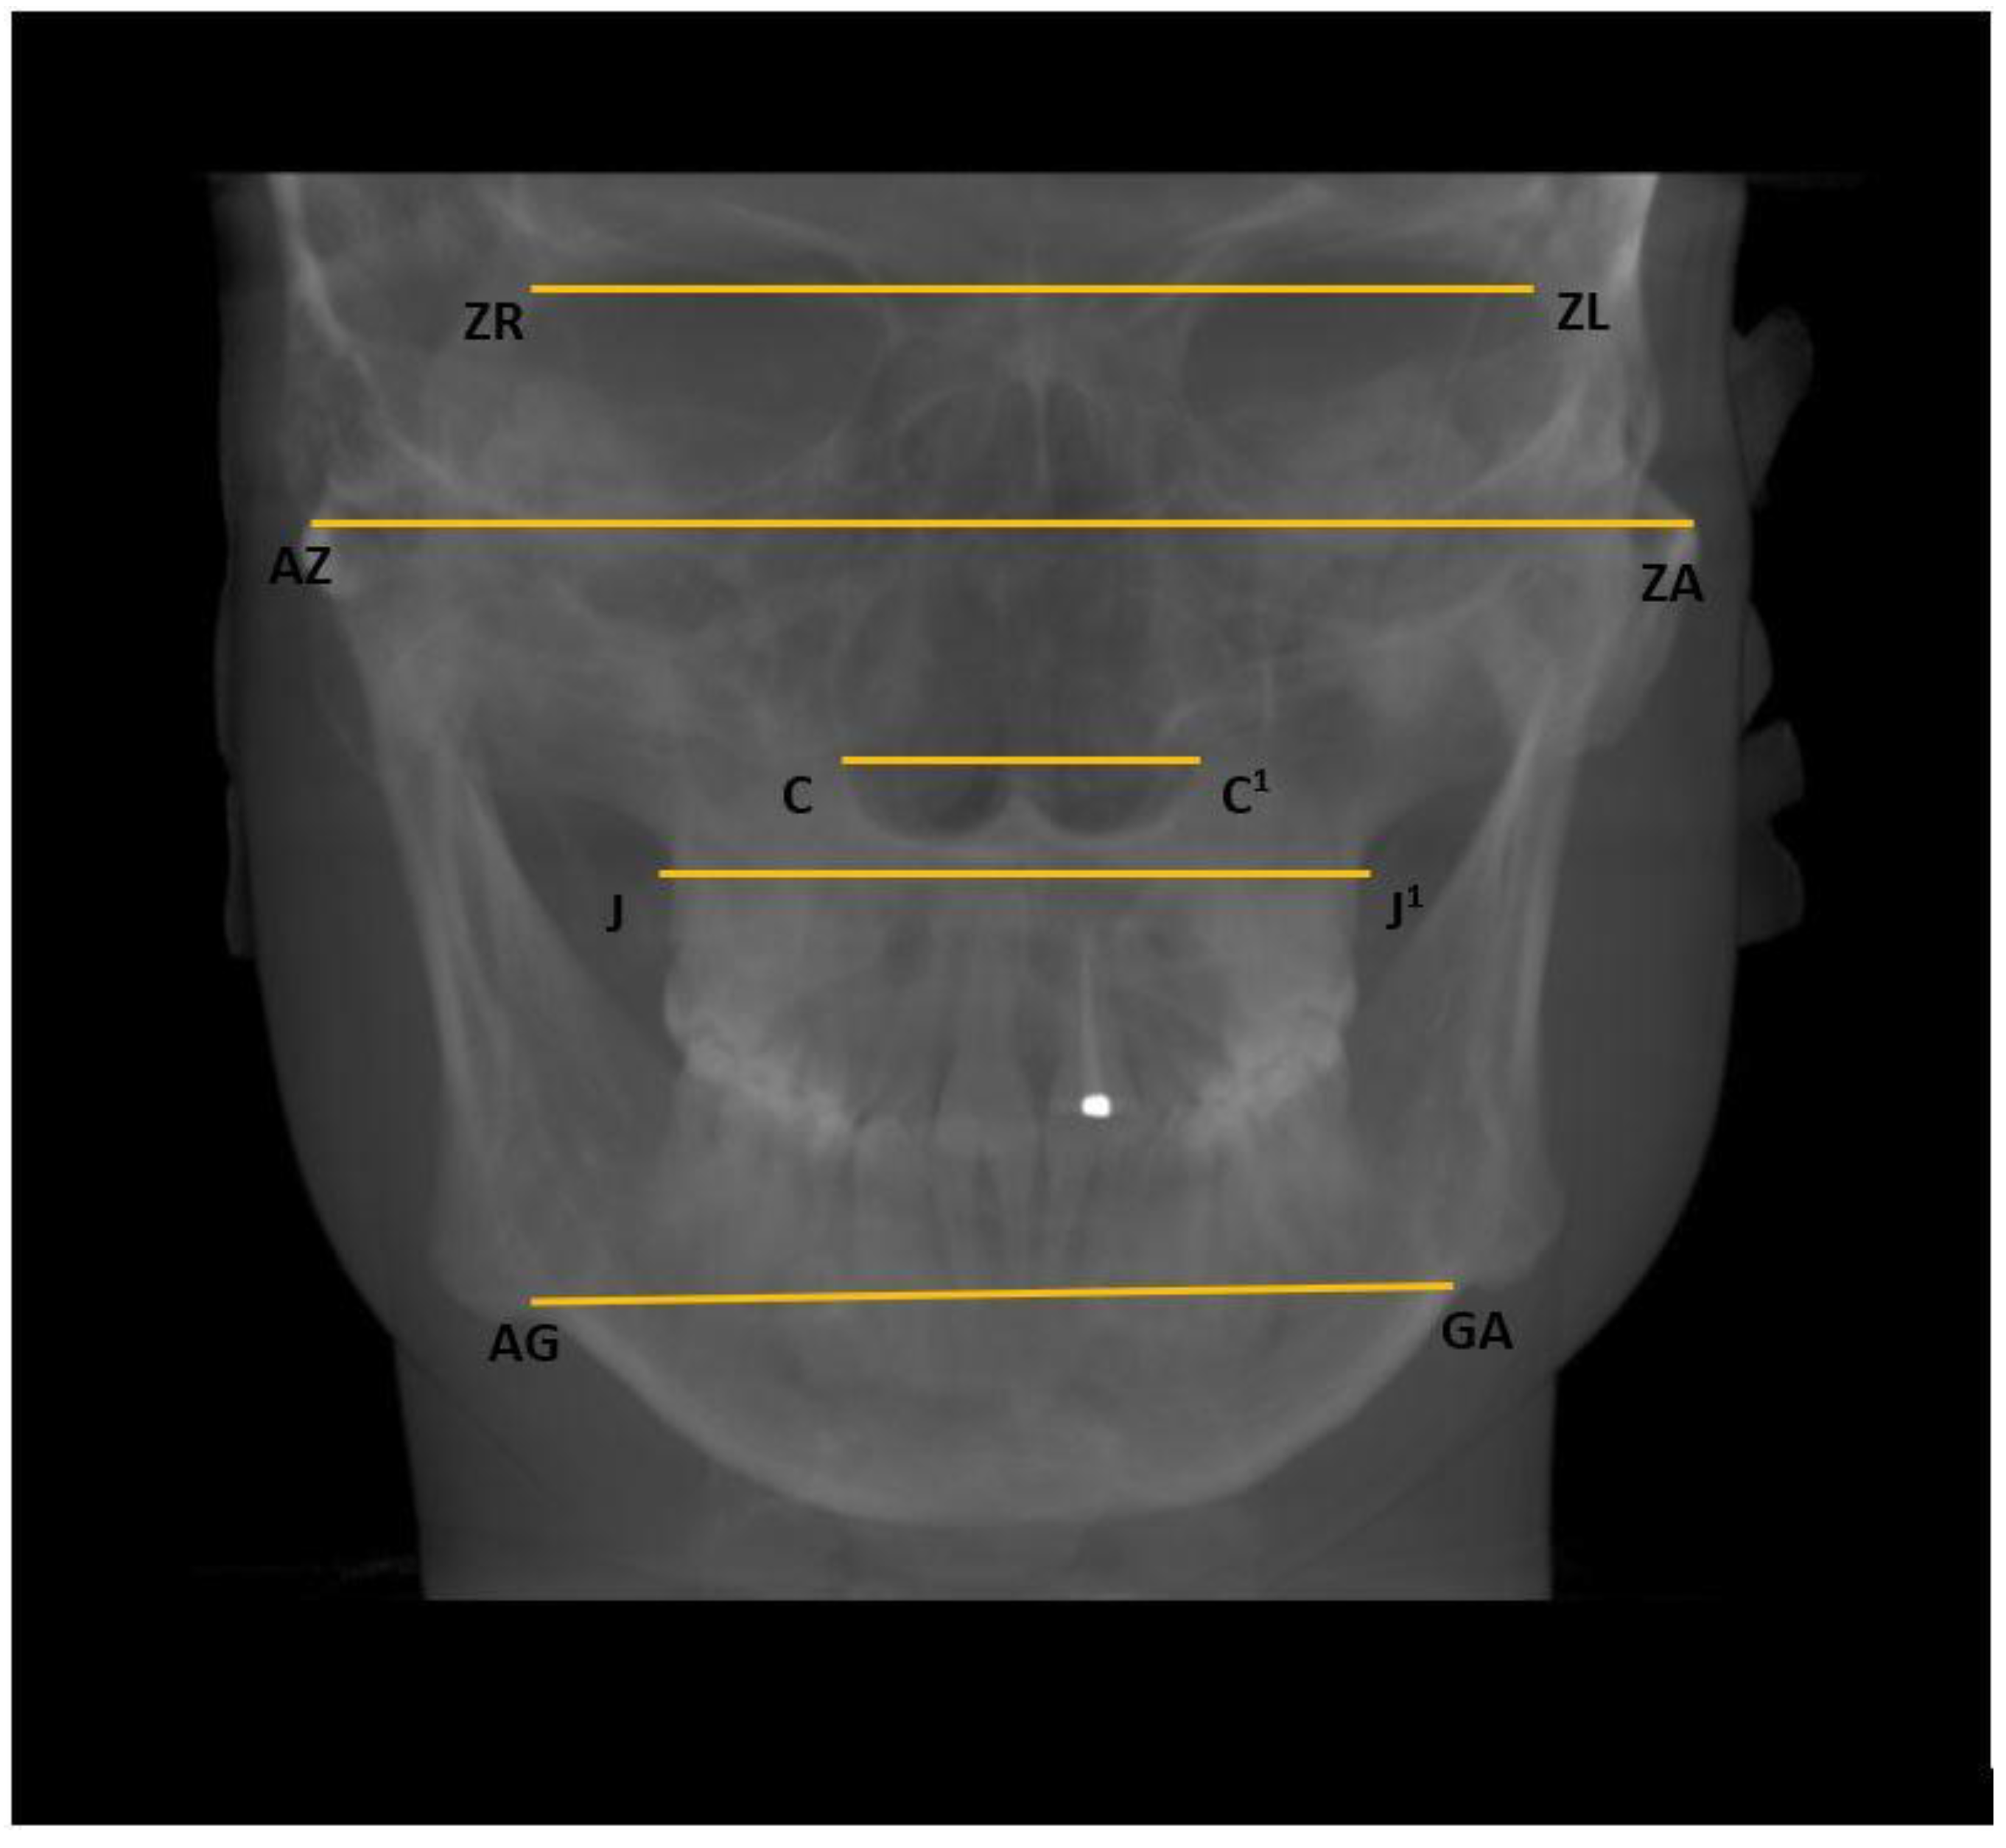

- Horizontal: Nasal cavity width (C–C1), distance between zygomaticofrontal sutures (ZR–ZL), distance between the centres of the roof of the zygomatic arch (AZ–ZA), distance between the jugal processes (J–J1), and distance between the antegonial points (AG–GA) (Figure 4);